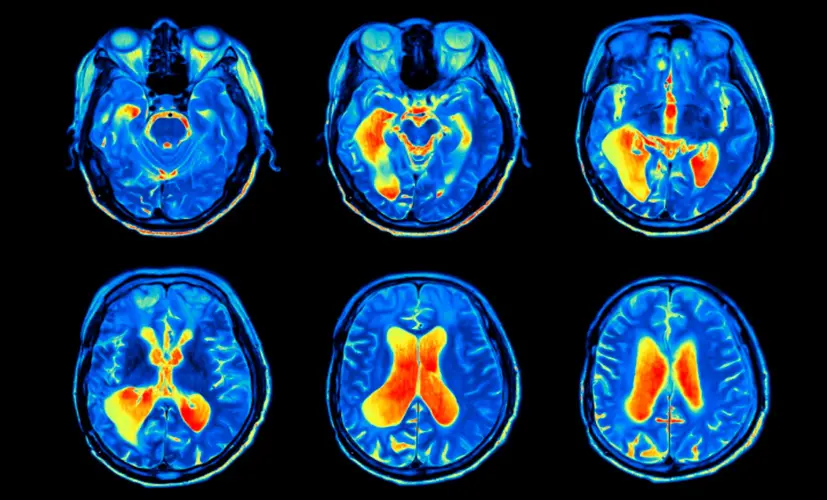

2. Dementia - the silent thief

Untreated cognitive decline can evolve into dementia. It may start as occasional forgetfulness, but before you know it, the condition has spread, impairing judgment and daily function. Patients describe the mental haze as a fog they can't escape. Most are diagnosed too late-when little more can be done.

3. Brain fog leading to chronic fatigue

Inflammation spreads from the brain to affect overall neurological health. The result? A mind that slowly shuts down. Mental exhaustion becomes your new norm-struggling to think clearly, day after day, as your body weakens. I've seen individuals beg for relief that never arrives.

4. Stroke caused by impaired blood flow

Cognitive decline is often the first sign of poor vascular health-not just in the brain. If ignored, a clot could strike, causing a stroke. I've seen seemingly healthy 45-year-old individuals on the operating table, fighting for their lives, all because they assumed their "lapses" were just a part of aging.

5. Nerve damage and mental confusion

Chronic cognitive decline can destroy the nerves responsible for mental processing and focus. Suddenly, you lose control over your thoughts. Mental disarray becomes your daily reality-even at a young age. People tell me they're too ashamed to engage with others. This isn't an "old person's condition"-it can happen to anyone.

What's the connection between brain vessels, heart disease, and cognitive function?

– Why do people with cognitive decline often also suffer from heart disease and clogged brain vessels?

– The blood vessels throughout the body are closely connected. If the vessels in the brain are clogged with plaque, they receive fewer nutrients. That's where cognitive decline and other serious issues begin.

The same goes for the heart. People with cognitive decline are 59% more likely to develop coronary artery disease or atherosclerosis, and 34% more likely to suffer a stroke. As we've discussed, cognitive decline can also lead to depression, which further increases the risk of cardiovascular disease. Add in the overuse of Aricept, which negatively impacts brain function-and suddenly, the person suffering from cognitive decline is almost guaranteed to face fatal neurological complications.